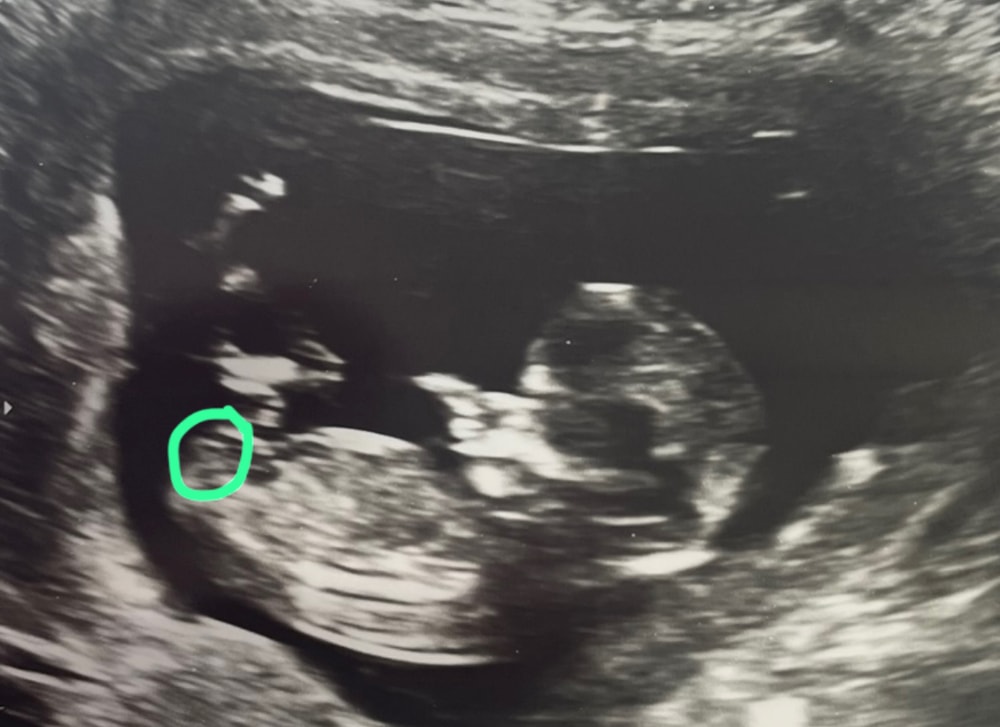

Светлана , то что вы и обвели. На моем узи +- тоже самое было. Девочку ждём

Мальчик на 3 и 4 фото

Алина, а где вы видите на 3 и 4 фото половой бугорок? Белая полоска или еще где-то?😀

Светлана , да, белая полоска

Светлана , да, вот то, что вы обвели рядом с белой полосочкой . А на нижних как бы за ней

Светлана, на нижних кроме этой белой полоски ни черта не вижу🤣